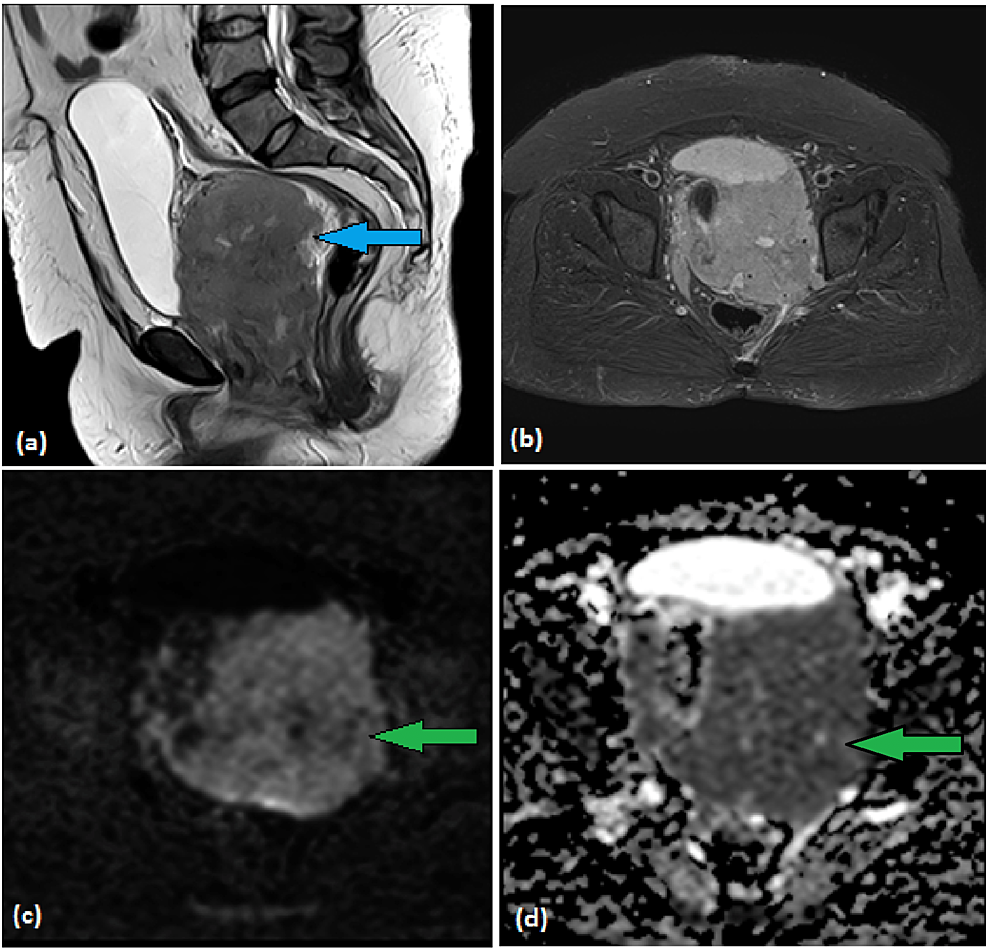

Vaginal non-Hodgkin's lymphoma (NHL) is a rare entity. We report a case of a 38-year-old lady who presented with complaints of lower abdominal pain for three to four months and vaginal bleeding for one month. Her examination under general anesthesia revealed …